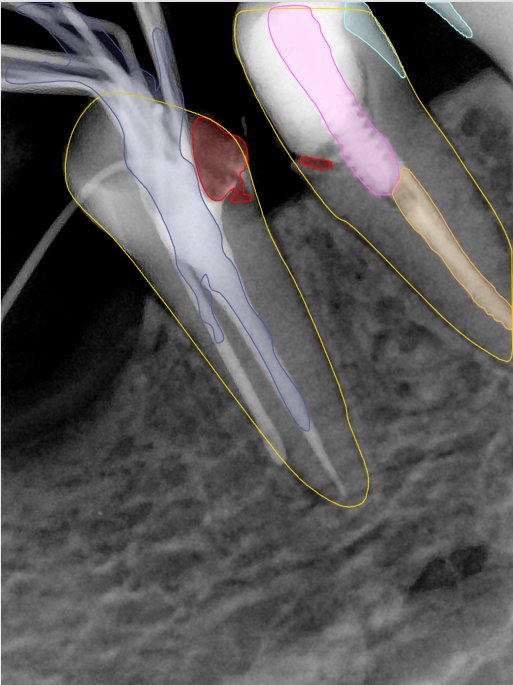

CR/DR 牙齿分割阶段记录

当前进展

- 完成了 CR/DR 牙齿相关分割训练

- 当前结果已经达到阶段预期,但仍有细节问题需要继续处理

相关测试

遇到的问题

- 训练过程中出现过 mask 下移问题

- 部分结果会出现 box 填充异常

- mask 边缘仍然有比较明显的锯齿感

参考

第二版算法问题测试